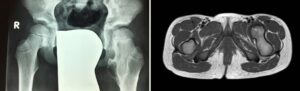

Exostosis (or osteochondroma) is a very common benign lesion in children, characterized by the formation of a hard protuberance that arises from the bone surface, usually near one end of a bone segment. More precisely, exostosis is a hamartoma of the growth plate, that is, a portion of cartilage that normally contributes to bone growth. In this case, it grows in an abnormal location and direction . However, it behaves similarly to the rest of the cartilage: starting from the cartilage at the apex of the protuberance (cartilaginous cap), it tends to progressively become bone (enchondral ossification), thus causing the exostosis to grow .

Solitary exostoses are most commonly located on long bones (distal femur, proximal humerus, proximal tibia), at the metaphysis, that is, immediately above the growth plate of that bone segment. They can vary greatly in shape and size; the base can be broad (sessile) or narrow (pedunculated).

Hereditary multiple exostoses (HME)) is a rare condition (incidence of 1-2 cases per 100,000 inhabitants) characterized by the formation of exostoses in different parts of the body.

These lesions are mostly located in the metaphyses of long bones, but frequently also in the scapula, ribs, and other areas.

Depending on the anatomical location , the radiographic morphology of exostoses tends to be different: for example, at the level of the lower (distal) part of the femur, exostoses tend to take on a pedunculated appearance in the proximal direction, at the proximal tibia they tend to take on a pedunculated appearance in the distally direction, at the level of the fibula and humerus they tend to take on a sessile appearance, at the level of the ulna they tend to locate in the distal part of the segment (towards the wrist) and cause shortening of the bone.